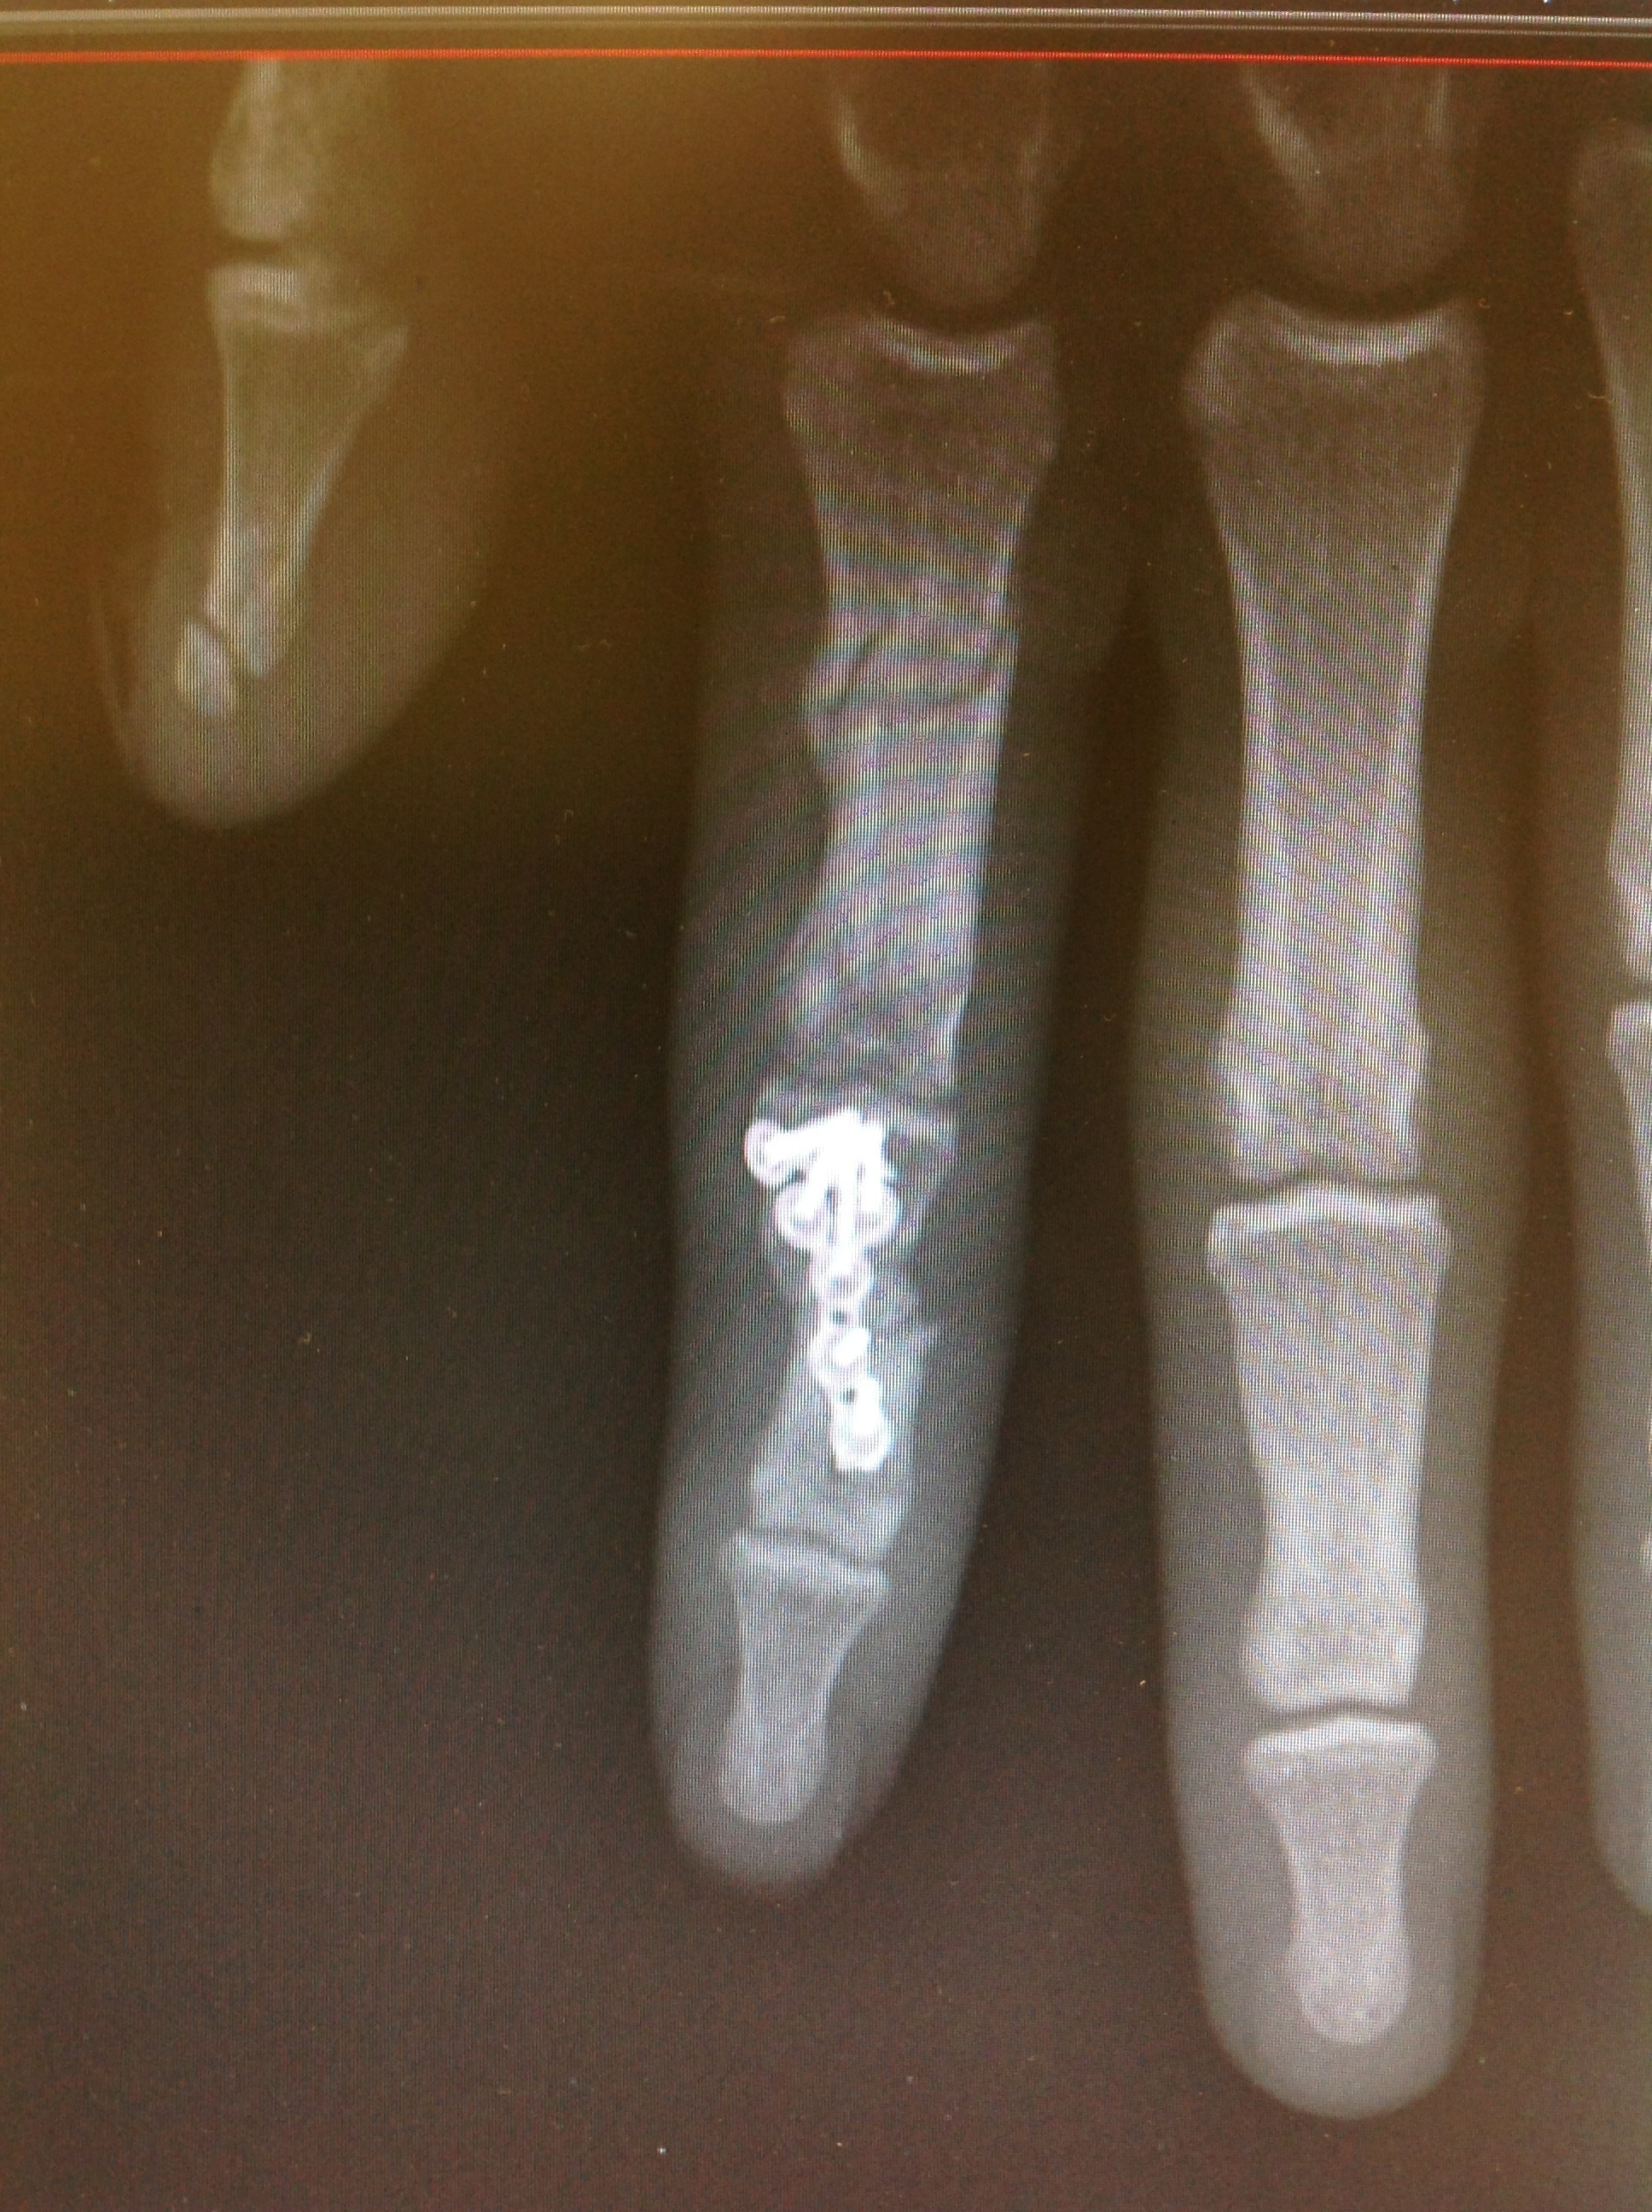

Se procedió a síntesis anterógrada de la F1 con 2 agujas de Kirshner introducidas con la articulación metacarpofalángica en flexión máxima para no limitar la rehabilitación precoz.no coloqué placa de síntesis pues tengo comprobado que en la F1 las placas dan lugar a gran número de rigideces que obligan a su retarda y a tenolisis. En la F2 conminuta procedí a colocar placa con injerto de radio, en lidera rotación radial para facilitar la pinza término-terminal de un índice que por la lesión del aparato extensor asociada ya se preveía que tendría poca mobilidad de IFD. Se inició kinesiterapia activa autoasistida a los 3días postop.

Se retiraron las agujas tras consolidación de la F1.